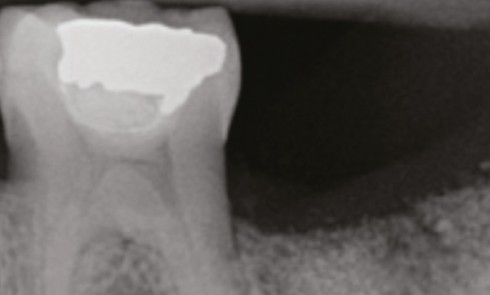

Article réservé à nos abonnés GuttaCore ou cross-linked gutta percha

LA GUTTA PERCHA La gutta percha (GP) est un polymère linéaire (de poids moléculaire de 30 000 à 60 000) dont le motif...